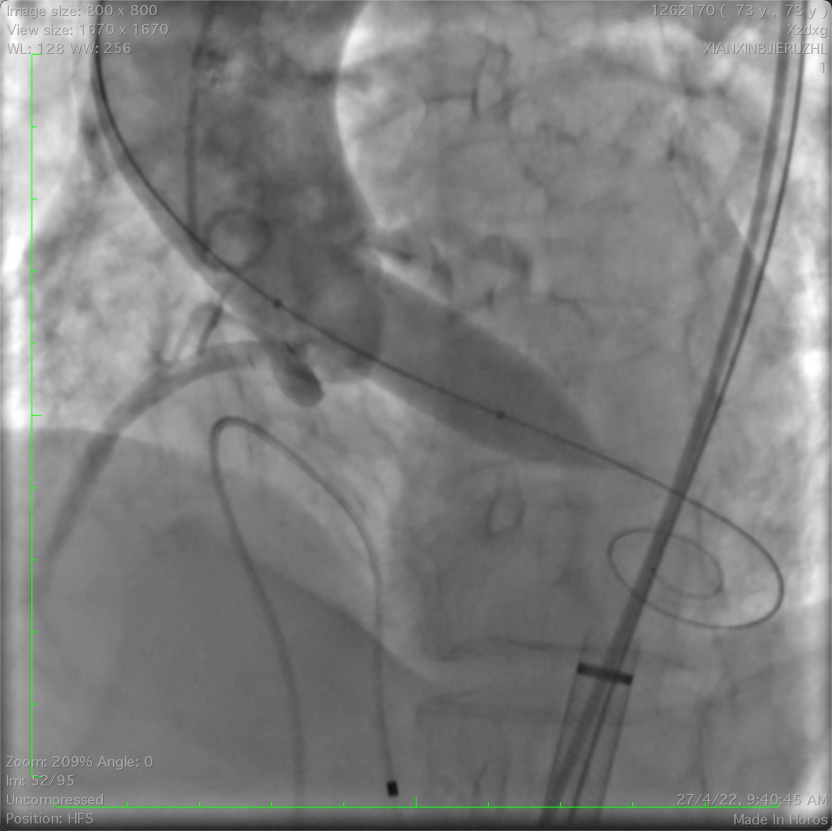

冠脉保护下释放瓣膜

图片

左冠口疑似遮挡

IVUS检查冠脉开口,

进一步精准评估冠脉开口遮挡情况

IVUS检查提示因原瓣叶遮挡,左冠开口受阻,最窄处残余缝隙0.66-0.82mm。